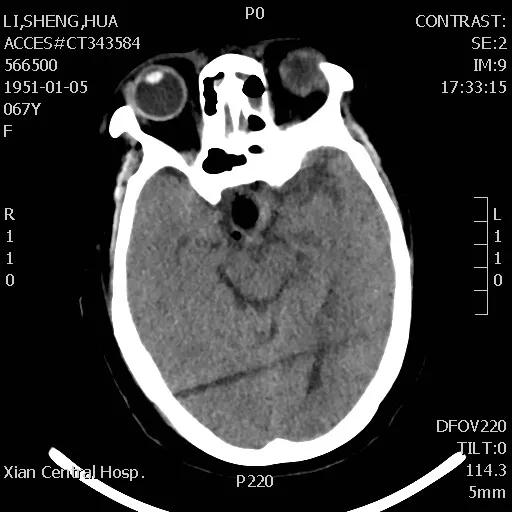

李女士头痛一年多,近日头痛加重并伴有视力迅速下降的症状,经朋友介绍,来到21点玩法研究所 神经外科王占尧主任医师处就诊。王主任通过与病人深切交谈,了解其既往病史、生活习惯、家族病史等后,均未发现有何异常,王占尧主任医师立即成立诊疗小组对李女士的情况进行分析并制定了神经内镜下手术的治疗方案。

手术于次日下午进行,整个过程非常顺利,患者预后也非常理想,术后复查CT显示肿瘤切除干净,患者视力改善明显,经过一段时间的后续治疗,患者已痊愈出院。